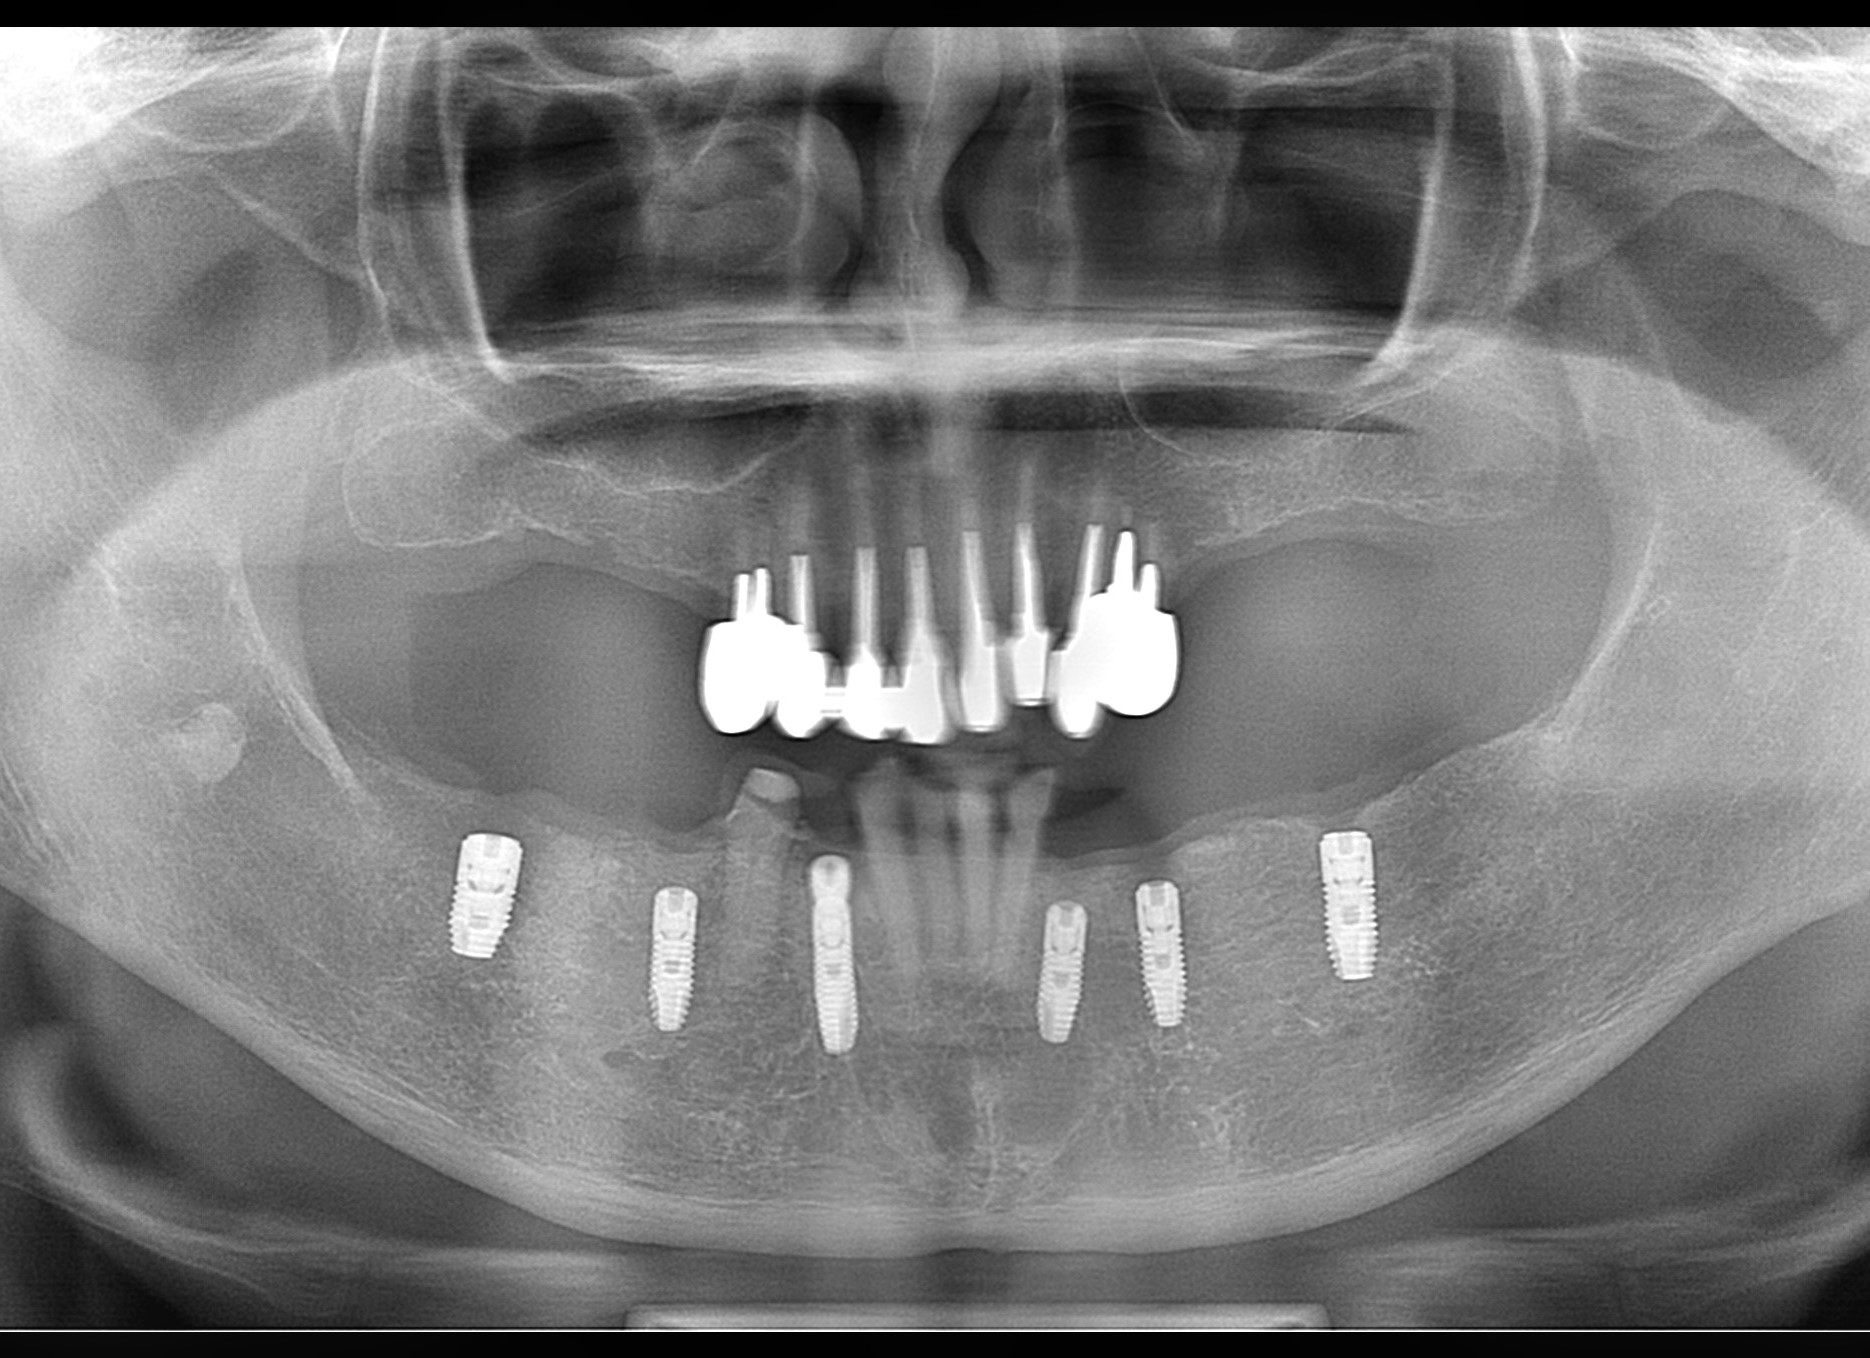

写真は、50代の女性です。ガイドシステム使い、1回の手術で5本のインプラントを埋入する手術を行いました。結果的には無事埋入できたのですが、予想以上に時間がかかりました。

P2.pano